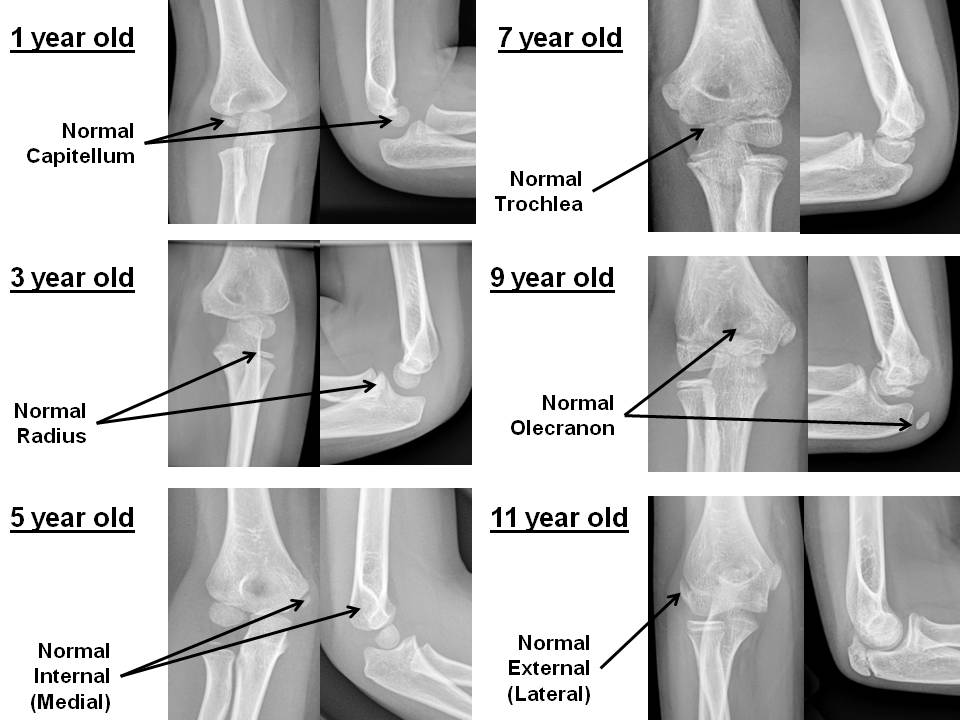

The sequence of apophyseal ossification about the elbow is abnormal. [Yes/No]

The secondary ossification centers are abnormal in size, shape, or position. [Yes/No]